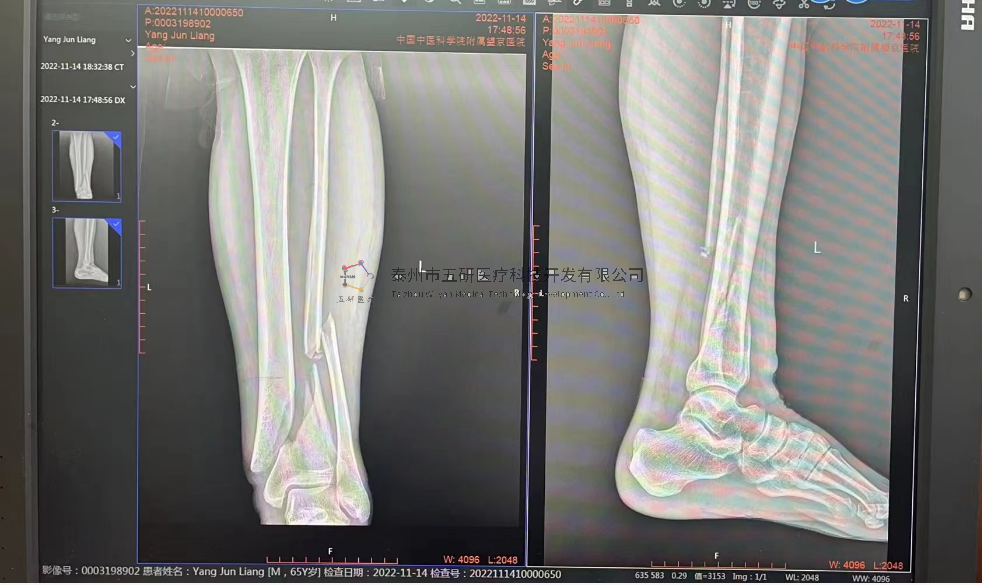

// 下肢骨折

【所屬科室】中國中醫(yī)科學(xué)院望京醫(yī)院創(chuàng)一科

【基本資料】患者,男,65歲

【患者情況】脛骨遠端骨折伴腓骨骨折

【影像圖片—術(shù)前】